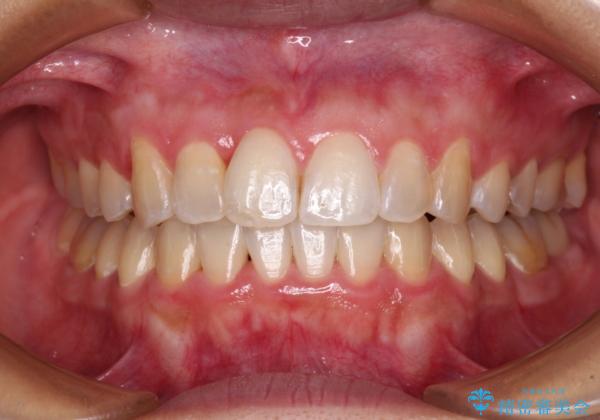

前歯のデコボコをインビザラインでスッキリと仕上げる

- 上下前歯のデコボコと奥歯の銀歯を気にして来院された患者様です。

口元をインビザラインにより歯列を整え、その後に失活している奥歯をオールセラミッククラウンにて補綴治療することとしました。

長時間のマウスピース装着に協力いただき、自然な口元に仕上げることができました。

気になっていた銀歯もオールセラミッククラウンで本物の歯のようになり、患者様には大変満足していただきました。